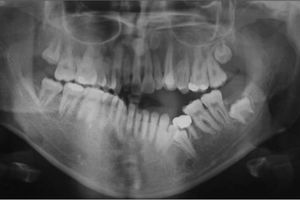

مشکلات دندانی: برای بررسی دندانها، فک و تشخیص مشکلاتی مانند پوسیدگی و عفونتهای دندانی استفاده میشود.